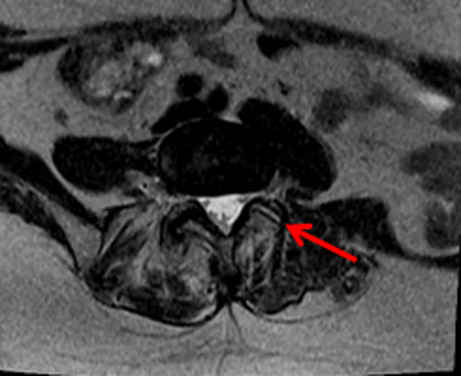

La conferma diagnostica arriva dalla indispensabile risonanza magnetica: si va dai reperti di sinovite fino ai più avanzati stadi di osteartrite di più faccette.

A complicare però il tutto è la possibilità di una mancata correlazione tra quadro clinico e quadro radiologico e quindi la possibile esistenza di una sindrome faccettale in assenza di un quadro radiologico tipico.

Il primo passo è quello di effettuare un “blocco nervoso” momentaneo utilizzando generalmente una soluzione di anestetico e cortisone, sotto guida radiografica o ecografica.

Tale blocco può avvenire o a livello del ramo dorsale o a livello intra-articolare.

Tale procedura rappresenta la prova del nove della diagnosi di sindrome delle faccette articolare: se avviene una risposta in termini di scomparsa o decisa diminuzione del dolore presentato, significa che l’ipotesi diagnostica è corretta.